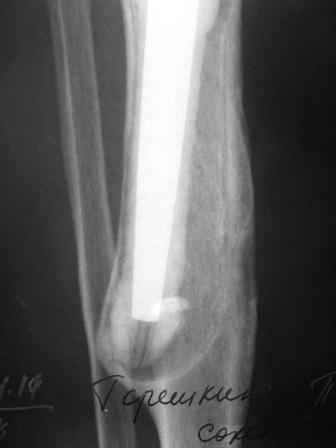

Нестабильность эндопротеза коленного сустава

Уважаемые коллеги! Хотелось бы услышать Ваше мнение о возможности и способе помощи больной. 1939 г.р. В 1995г. эндопротезирование правого коленного сустава протезом Феникс, в 1999г. в г. Томске - ревизия - ротационный хинч W.Link.

C 2005г. прогрессирует варусная деформация за счет нестабильности тибиального компонента. Попытка ортезирования - без эффекта. Попытка направить в ФСМУ без эффекта, да и больная не хочет никуда ехать. С уважением, Leonid